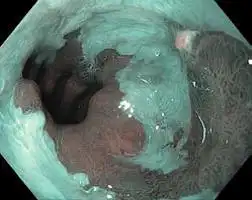

NBI (Narrow Band Imaging)

NBI in EVIS EXERA III 190 Series scopes provides twice the viewable distance of EVIS EXERA II 180 Series scopes and offers much greater contrast between blood vessels and mucosa. The greatly improved performance of NBI opens up exciting new clinical applications and reinforces NBI’s position as the standard of care for GI endoscopy

White Light NBI